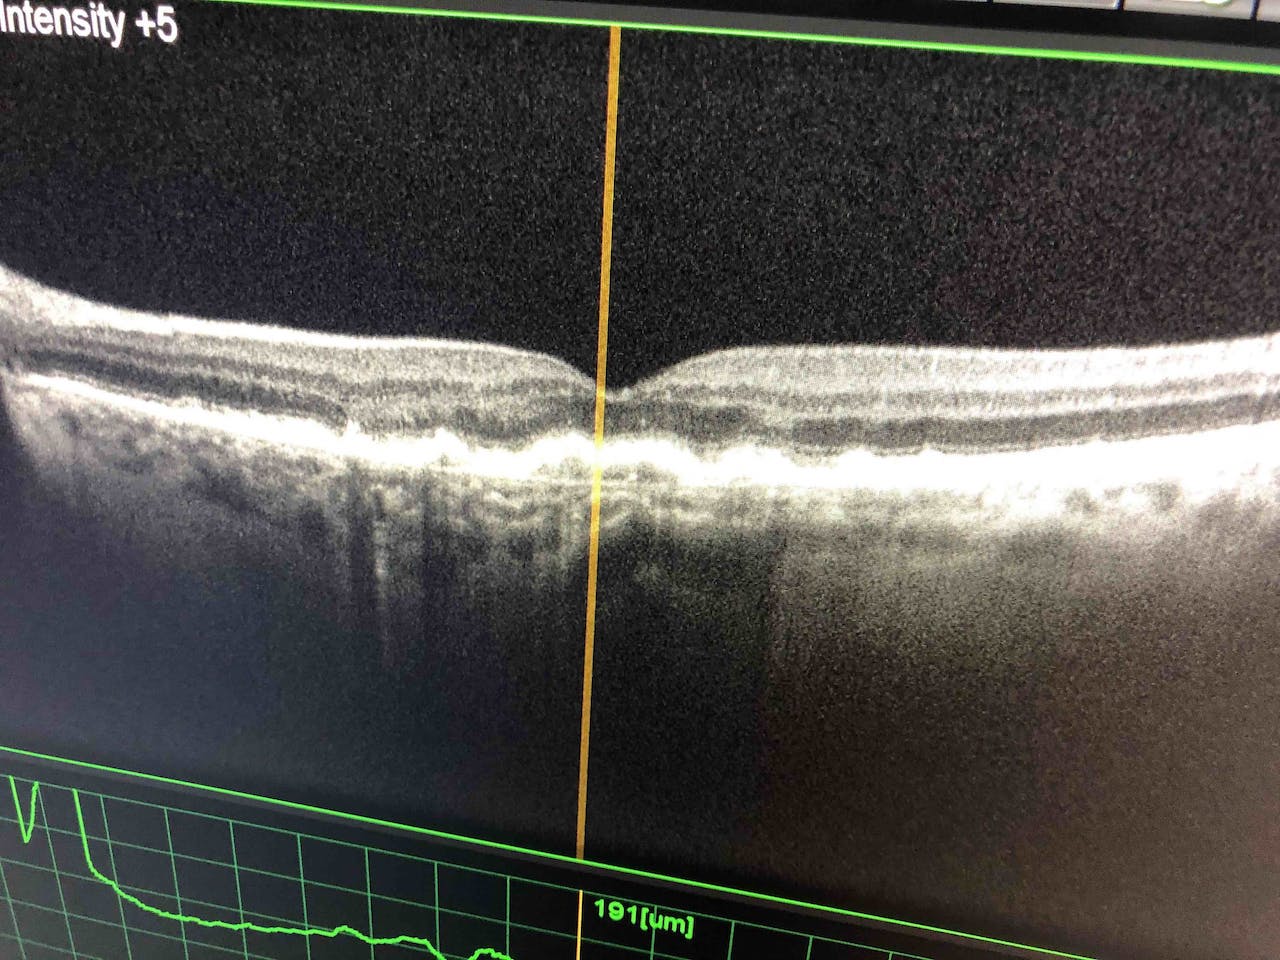

Examens préliminaires

Une série d'examens ultra-modernes est réalisée par nos techniciens pour évaluer votre vision et vos yeux.